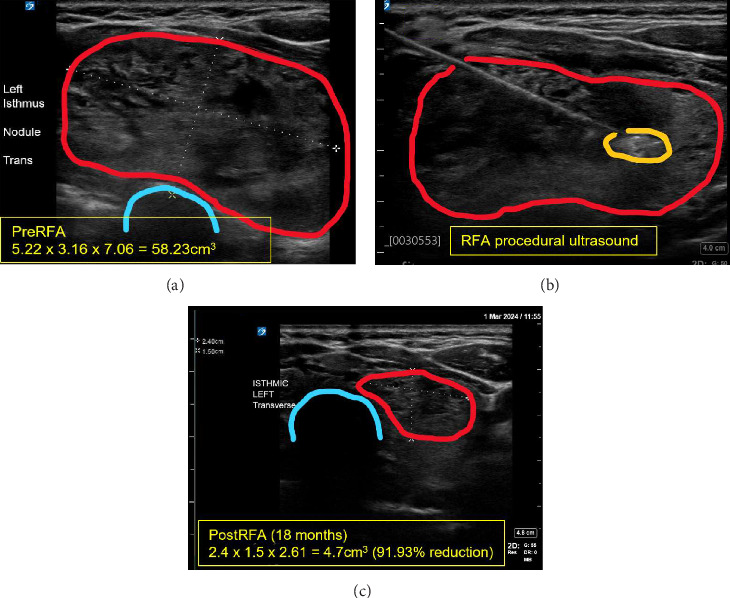

Background: Obstructive sleep apnea (OSA) and nontoxic multinodular goiter are conditions that often coexist. Treatments of both conditions have evolved over time, but continuous positive airway pressure (CPAP), oral appliances, or surgical therapy are often needed. Radiofrequency ablation (RFA) of the soft palate and base of tongue has been applied as a newer alternative therapy for OSA. RFA is also an increasingly used approach for thyroid nodules and goiter, but previously had no known connection to OSA. Case Presentation: A 59-year-old female with a known history of multinodular goiter and moderate OSA was referred to our endocrine surgery clinic. The goiter was found to have mediastinal extension, documented longitudinal growth of the dominant nodule, cosmetic deformity of the neck, and tracheal deviation. The patient underwent thyroid RFA as nonoperative treatment for her goiter. Within a month of her procedure, she also self-reported a subjective reduction in apneic events and later underwent a formal home sleep study demonstrating an apnea-hypopnea index (AHI) change from 15.8/h at diagnosis to 2.9/h currently, signifying resolution of her OSA. Her treated nodule had 92% volume reduction on 18-month follow-up visit. Conclusion: To our knowledge, this is the first reported case of OSA cured in a patient undergoing RFA for goiter. Goiter-associated sleep apnea remains inadequately described in the literature and warrants further investigations on prevalence and management. Thyroidectomy continues to be the definitive treatment for goiter, with some studies suggesting secondary efficacy for OSA. RFA is now established as a first-line option for symptomatic thyroid nodules, but previously had no described benefit to OSA symptoms. This report illustrates that RFA of thyroid nodules could be offered to patients as both an effective nonsurgical option for goiter as well as a potential cure for their OSA to free them from nightly CPAP usage.

Abstract Image